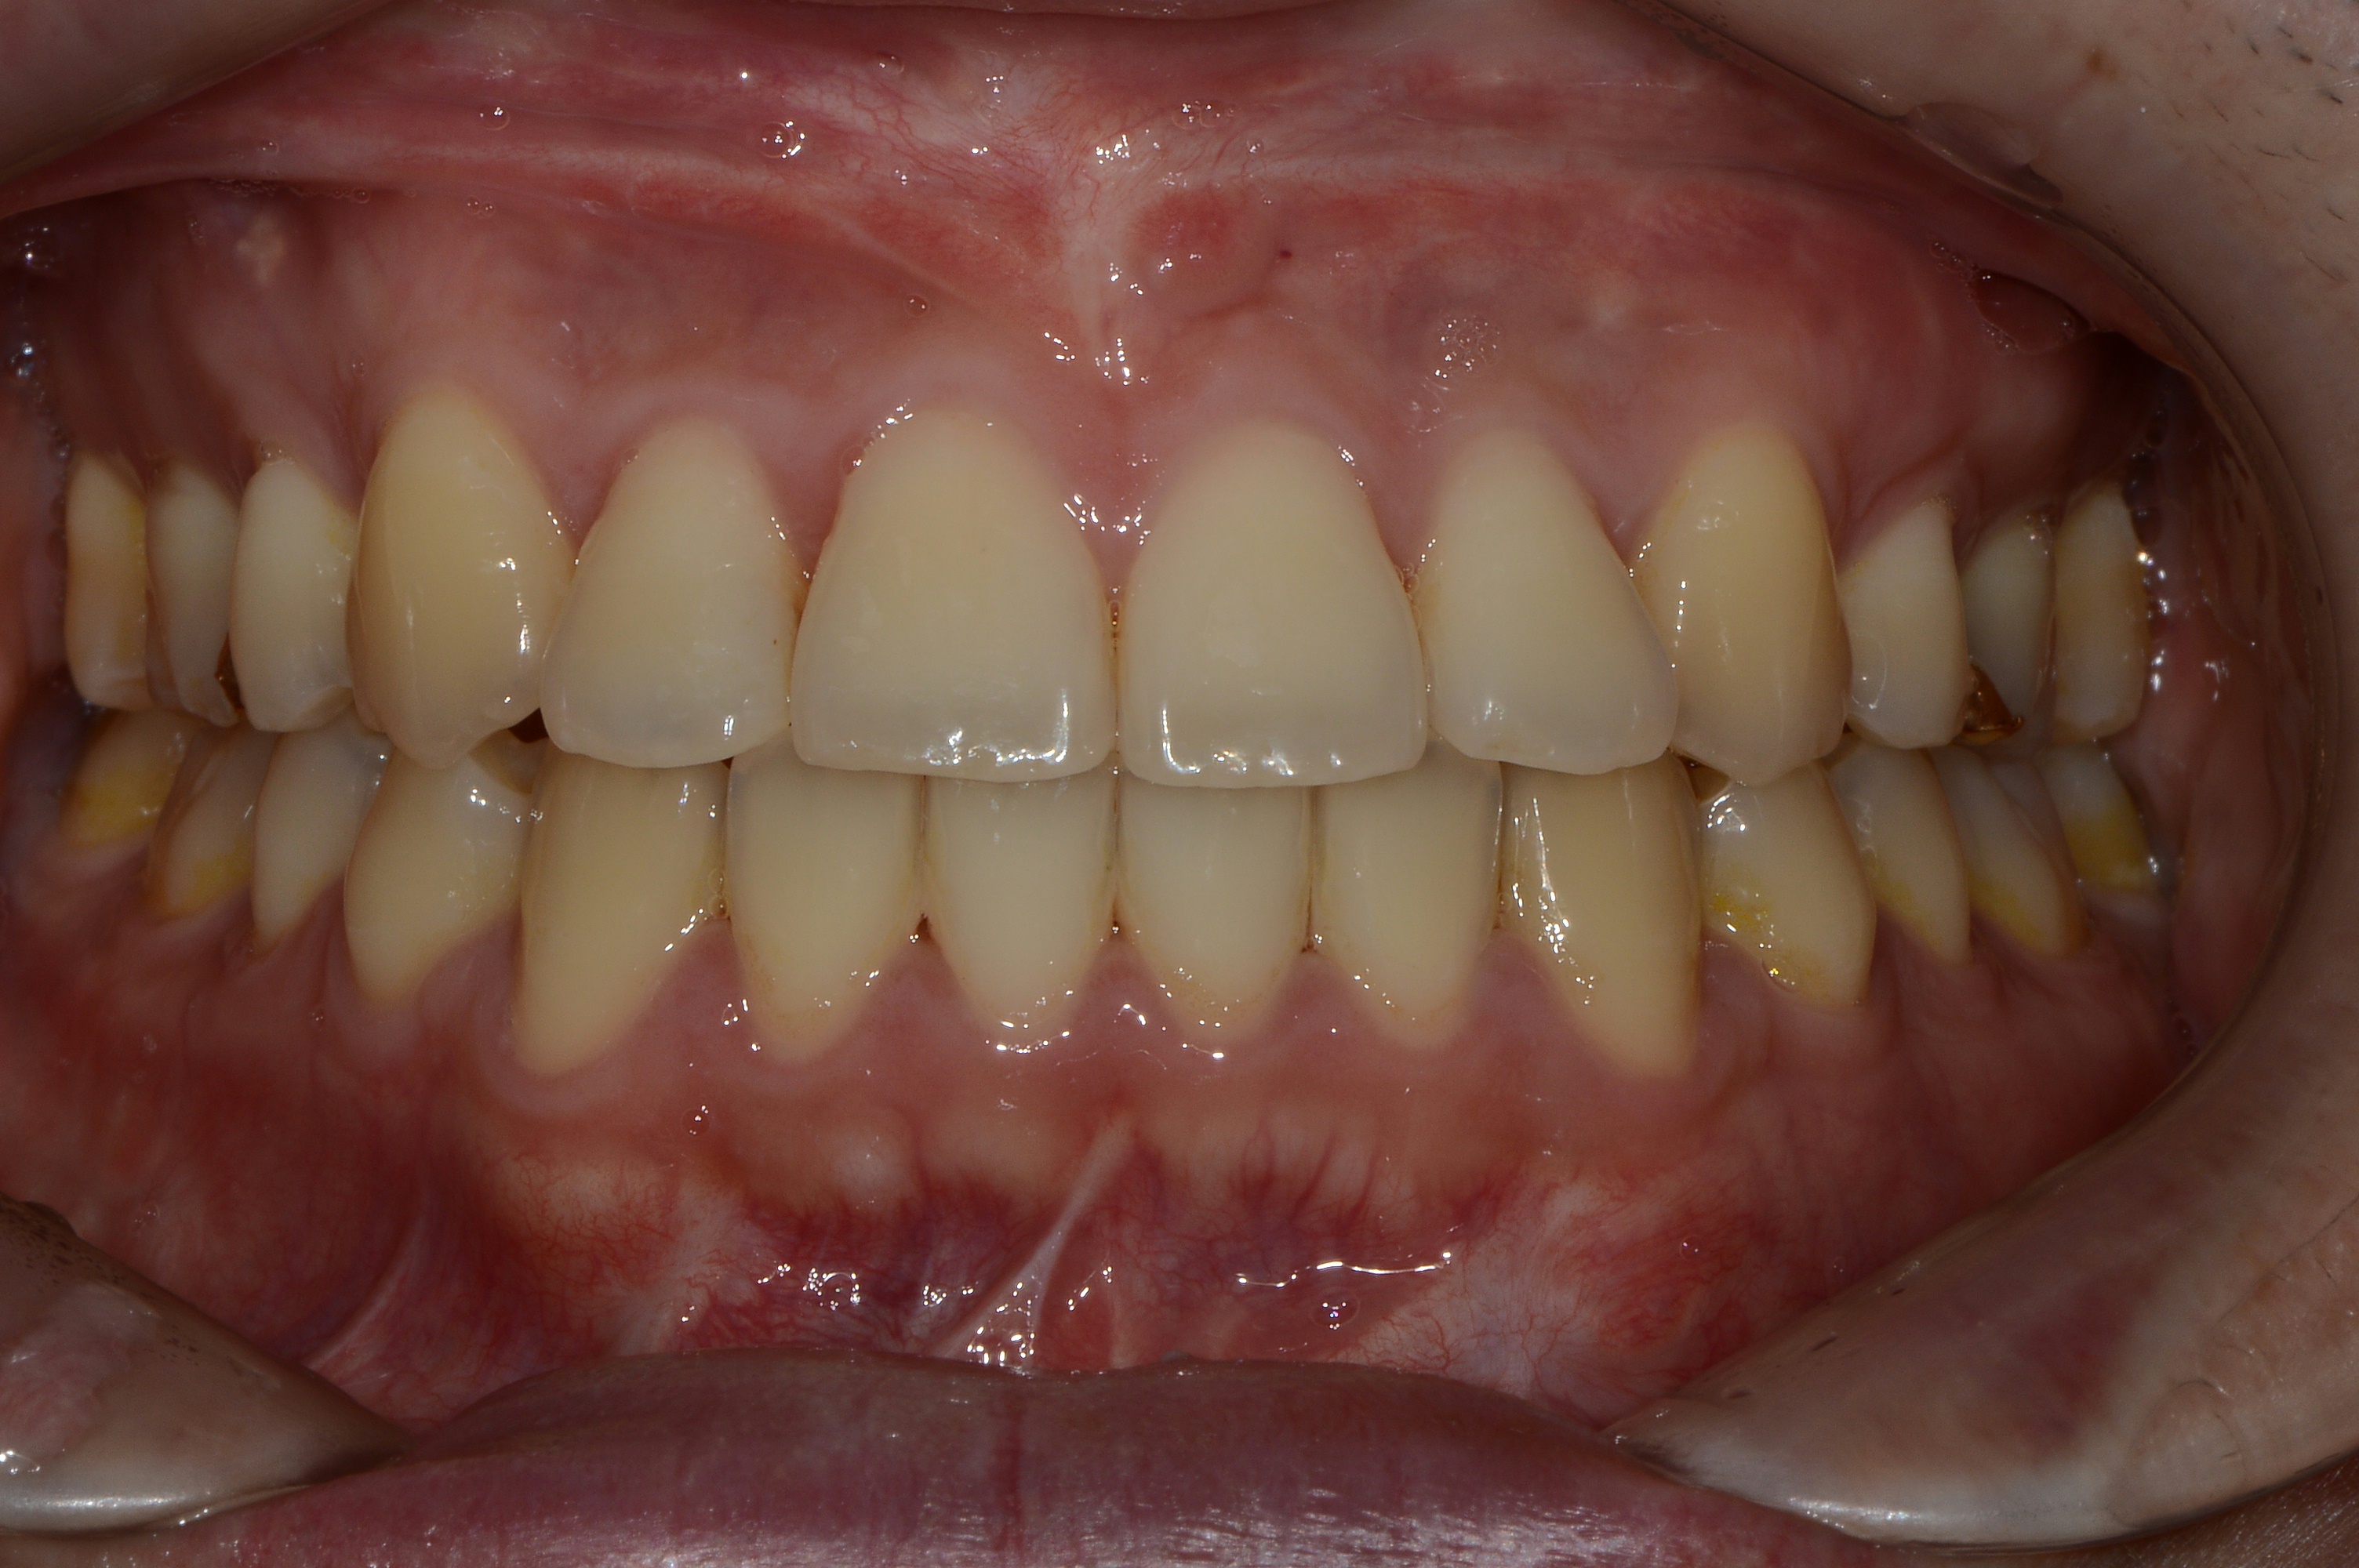

치료 후 사진입니다.